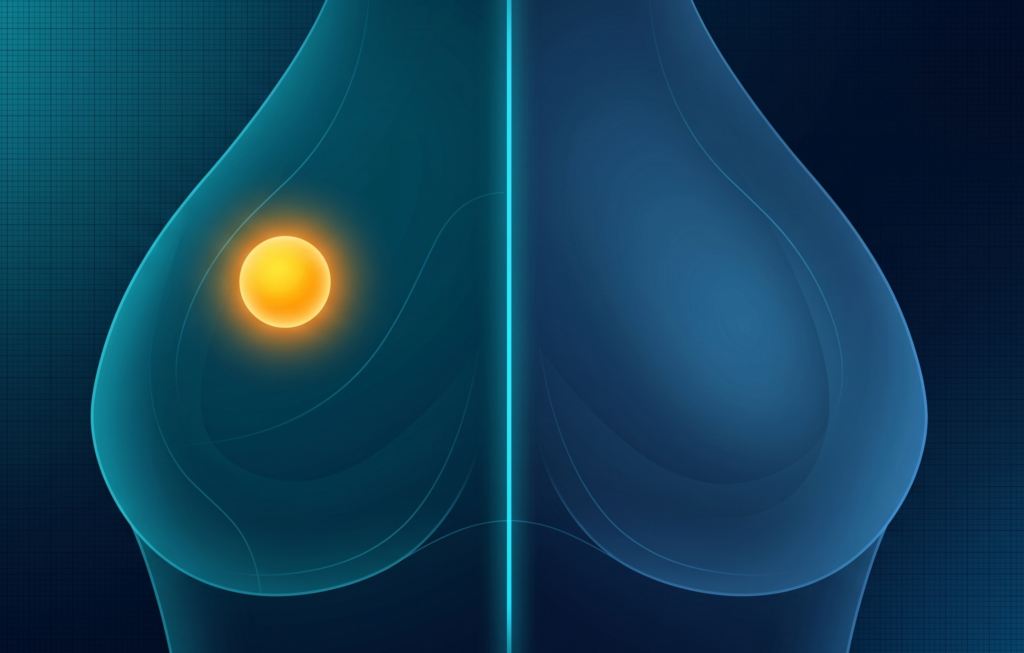

MBI’s Middle Ground

Molecular breast imaging continues to gain traction as an efficient supplemental screening tool, balancing clinical utility with ease of implementation for rads and patients alike.